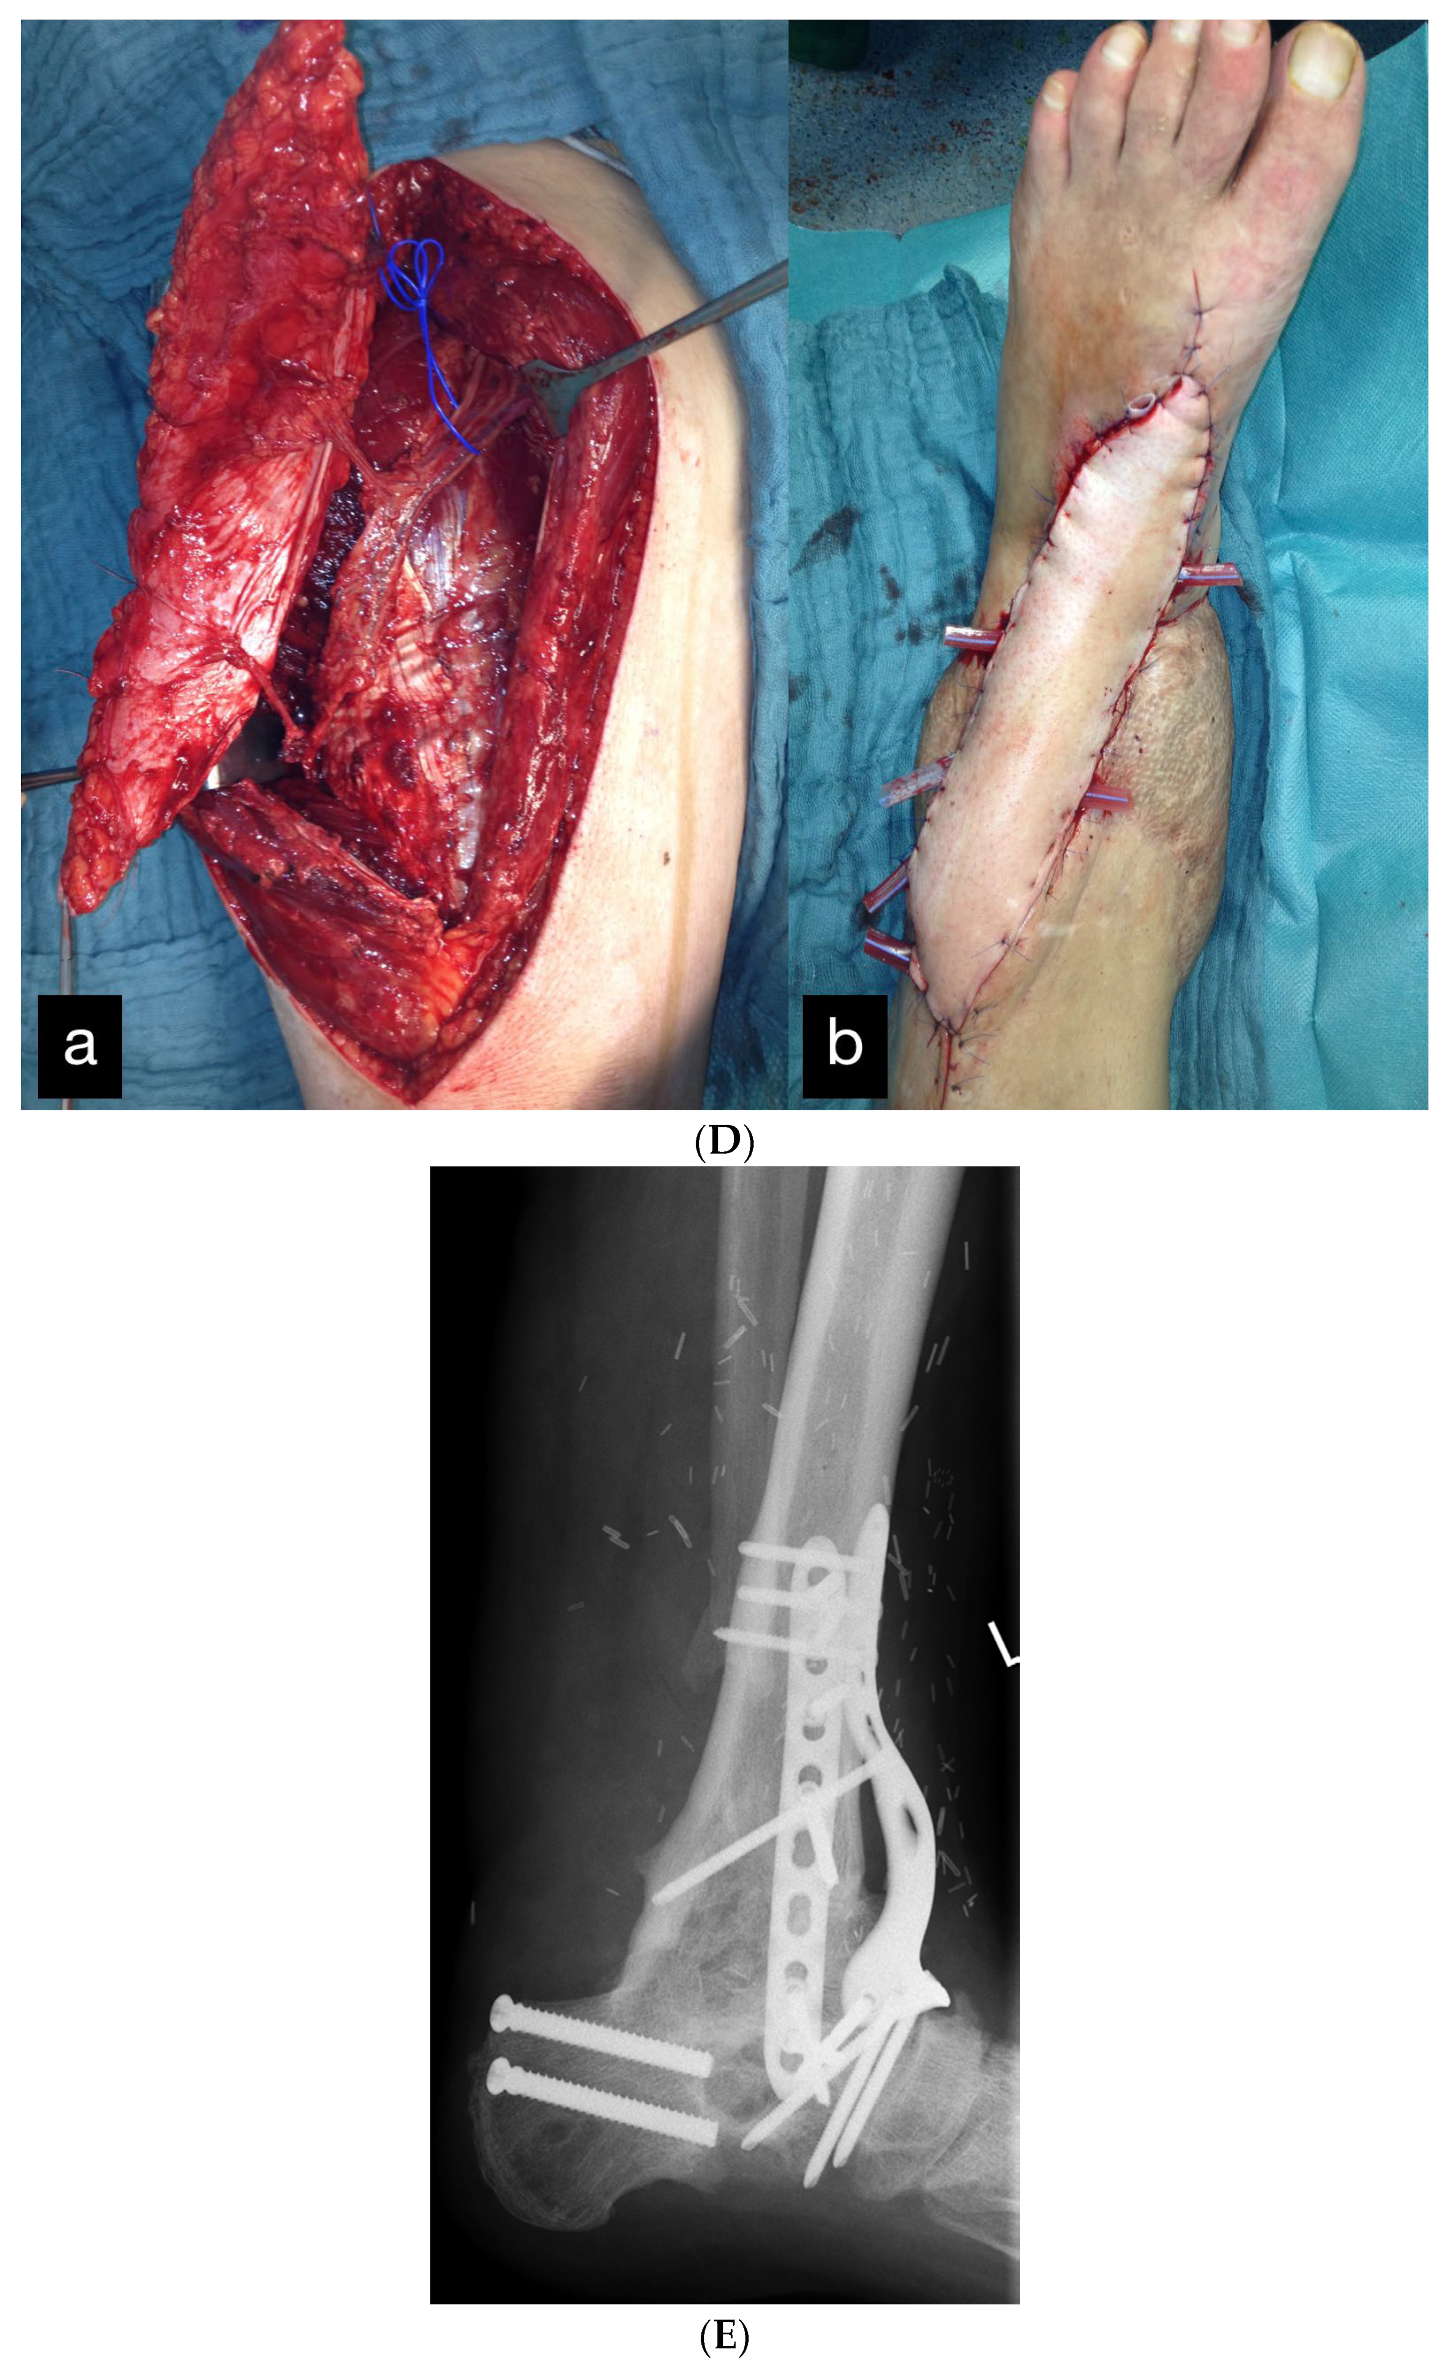

| 2 | 45 | m | Amputation of the left lower leg because of trauma caused by a steel beam | Initial replantation, Free latissimus dorsi flap, Free ALT flap for ventral defect arthrodesis OSG with vascularized iliac crest | Full weight bearing possible. No ROM OSG because of arthrodesis. | Improvement in sensitivity in the sole of the foot, as well as deep sensitivity in the area of the flap | - |